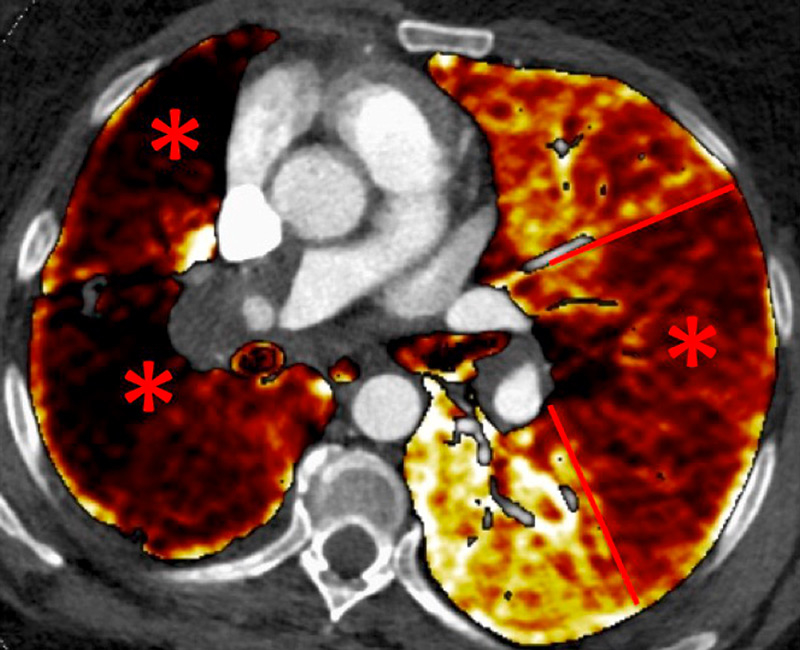

Figure 3

Chronic thromboembolic pulmonary hypertension (CTEPH). Segmental occlusions of pulmonary arteries (arrow) in the pulmonary angiography (A) are clearly visible on the CT angiography (B), with normal lung (C), and responsible for triangular perfusion defects (arrows) on the perfusion maps (D) confirmed by the ventilation-perfusion scintigraphy (E–F).